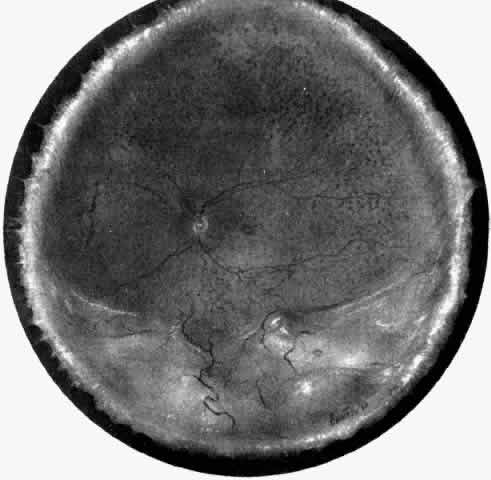

Fig. 1. Painting of the ophthalmoscopic features of uveal effusion syndrome. There is a diffuse pigmentary disturbance in a dot, blot, or linear configuration and an annular ciliochoroidal effusion with secondary inferior retinal detachment.

The pathogenesis of uveal effusion syndrome (Fig. 18), also referred to as idiopathic ciliochoroidal effusion, has not been clearly defined, but it is now thought to be primarily due to an abnormality in scleral thickness.92 It is usually unassociated with any other ocular or systemic abnormalities and occurs in the noninflamed eyes of middle-aged men as an insidious, progressive, usually bilateral non-rhegmatogenous retinal detachment with shifting fluid. This detachment can occur before there is any detectable ciliochoroidal elevation. Other findings include flat peripheral ciliochoroidal effusion, scattered retinal exudates, and localized areas of RPE hypertrophy and hyperplasia (“leopard spots”) (see Fig. 1).12,13,69,70,92,94 Evidence of uveal, retinal, or vitreous inflammation is minor or absent (see Fig. 18).